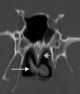

Turbinate enlargement